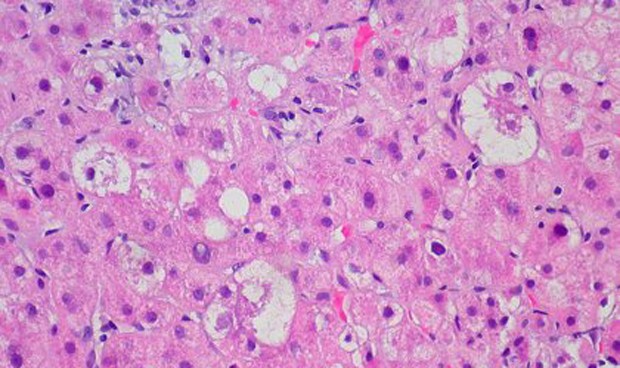

Una nueva investigación liderada y coordinada desde Barcelona por el profesor Jonel Trebicka e investigador clínico de la European Foundation for the Study of Chronic Liver Failure (EF Clif) ha identificado que las infecciones bacterianas y la hepatitis alcohólica aguda grave, tanto de manera independiente como en combinación, son los principales factores precipitantes tanto de la descompensación aguda de la cirrosis como de la insuficiencia hepática aguda sobre crónica (ACLF, por sus siglas en inglés), la fase más grave de la cirrosis.

Hasta ahora se pensaba que la descompensación aguda de la cirrosis se iniciaba por un empeoramiento agudo de la cirrosis estable a través de diversos eventos precipitantes. En 2013, el estudio 'Canonic' caracterizó el síndrome ACLF como el fenotipo más grave de la cirrosis descompensada aguda. Recientemente, la primera investigación del estudio 'Predict' ha demostrado que la cirrosis descompensada presenta diferentes fenotipos clínicos. Varias investigaciones derivadas de ambos estudios demuestran que la inflamación sistémica conlleva una disfunción multiorgánica, cuyo resultado son los distintos fenotipos, como el Pre-ACLF y el ACLF.